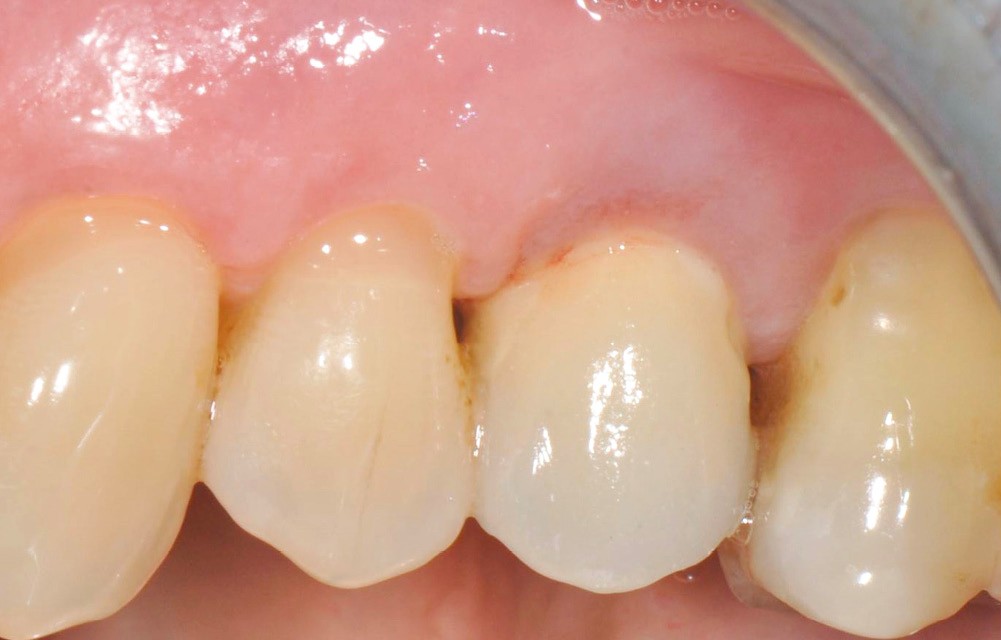

Chez cette patiente, le traitement de la péri-implantite a été réalisé à l’aide d’une technique de régénération osseuse guidée péri-implantaire, dont l’indication a été principalement motivée par la morphologie du défaut osseux. Au-delà de la maîtrise du geste chirurgical, le bon résultat obtenu à trois ans est intimement lié à sa coopération en termes de suivi et de contrôle de plaque.

13 et 14. À 3 ans, une régénération osseuse satisfaisante et un bel aspect des tissus péri-implantaires sont observés. Les poches font 3 mm en mésial, distal et palatin, et 2 mm en vestibulaire. Il n’y a pas de saignement au sondage.